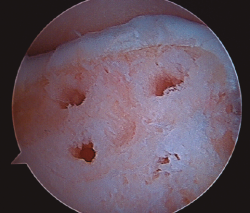

Figura 3. Secado de la articulación con aspirador.

- Una vez se completa el desbridamiento de la capa mineralizada, detenemos la infusión de suero salino y procedemos al secado meticuloso de la misma mediante aspiración y empleo de gasas y torundas (Figura 3).